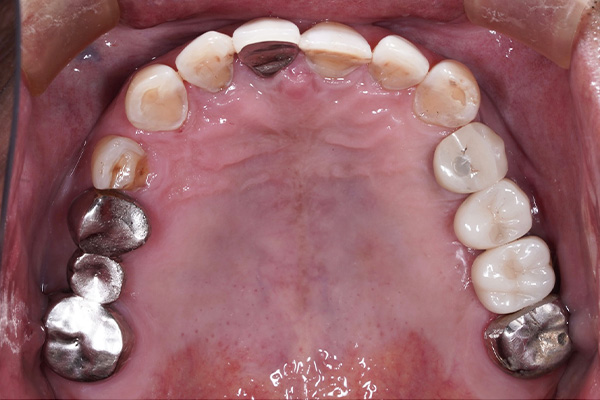

【お悩み】

奥歯を失ってから、食事の際にしっかり噛めず不便を感じていました。入れ歯には抵抗があり、インプラントを検討して来院されました。

【診断】

歯科用CT検査により、インプラントに必要な骨量が十分にあることを確認しました。

【治療内容】

骨造成は行わず、患者さまの状態に合わせたインプラント治療を行いました。

【治療後】

治療後は奥歯でしっかり噛めるようになり、食事のストレスがなくなったとお話しされています。

【この症例のポイント】

一般的な奥歯の欠損であれば、状態によっては比較的シンプルな治療計画でインプラントが可能なケースもあります。